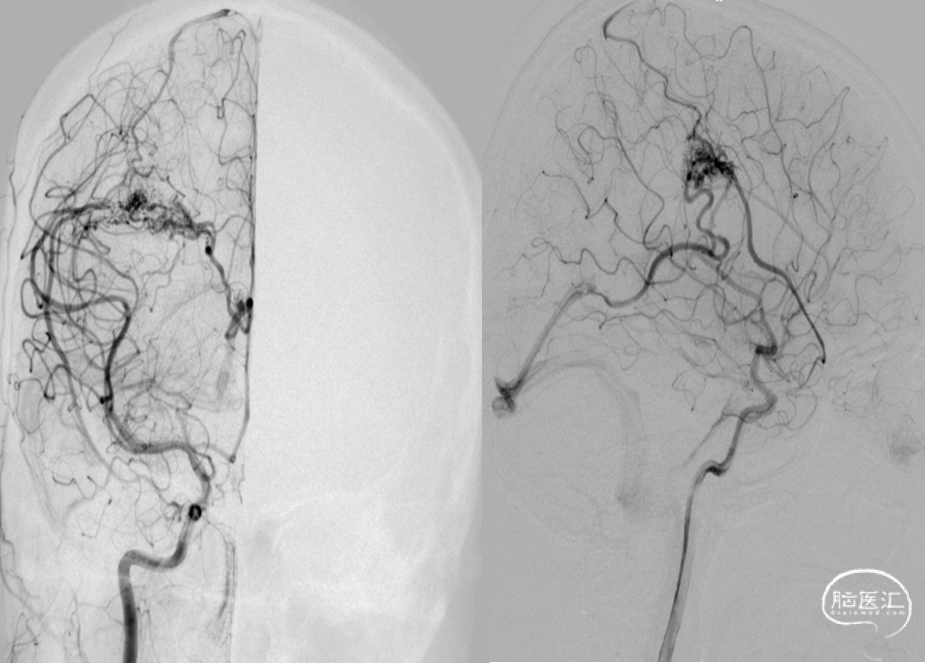

DSA:右侧额顶叶脑动静脉畸形

10个月DSA复查